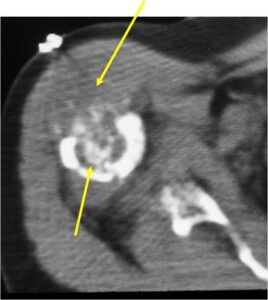

Radiology emulates pathology: Biphasic Tumor

- Second more aggressive area with bone destruction, lysis of calcification, soft tissue mass

- Cortical permeation and a soft tissue mass in 70% of cases

Ill-defined, lytic intraosseous lesion

- Or extraosseous soft tissue mass

Biological Behavior

- Very aggressive locally

- Frequently cortical perforation

- Mass is usually large if extraosseous extension occurs